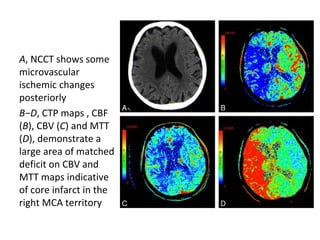

A, NCCT shows some

microvascular

ischemic changes

posteriorly

B−D, CTP maps , CBF

(B), CBV (C) and MTT

(D), demonstrate a

large area of matched

deficit on CBV and

MTT maps indicative

of core infarct in the

right MCA territory